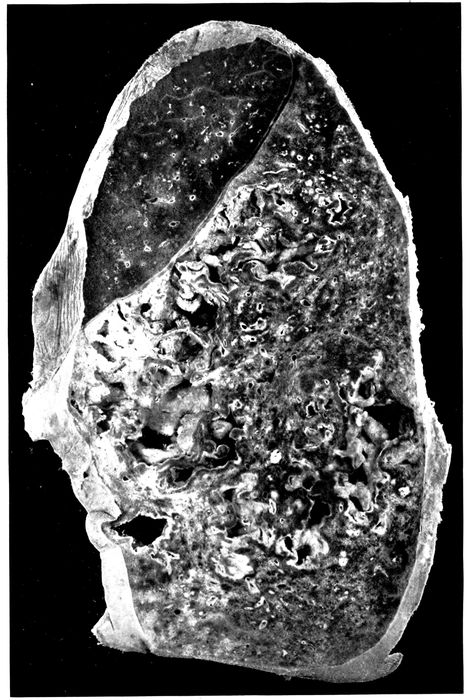

5. Bronchopneumonia with hemorrhagic peribronchiolar consolidation 174

6. Acute bronchopneumonia with confluent gray lobular consolidation in lower part of upper lobe and hemorrhagic peribronchiolar pneumonia in lower lobe; purulent bronchitis 180

25. Advanced bronchiectasis throughout lower left lobe 258